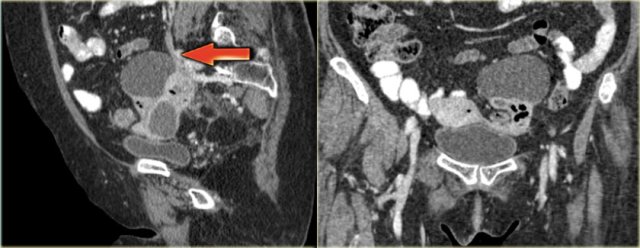

The axial CECT image shows a left complex cystic lesion with thick enhancing walls and internal gas.

It looks like an abscess.

Note the relatively unremarkable aspect of the overlying mesentery: this is unlikely to be a peri-diverticular abscess.

Continue with the reconstructed images.

On the sagittal image notice, that the lesion is connected to the ovarian vein confirming that this is an ovarian lesion (arrow).

The coronal image shows the anatomic connection to the uterus.

There is a gasbubble in the uterine cavity, which confirms the suggestion of an infection rising from the uterine cavity via the salphinx to involve the ovary (click or tap the image to enlarge).